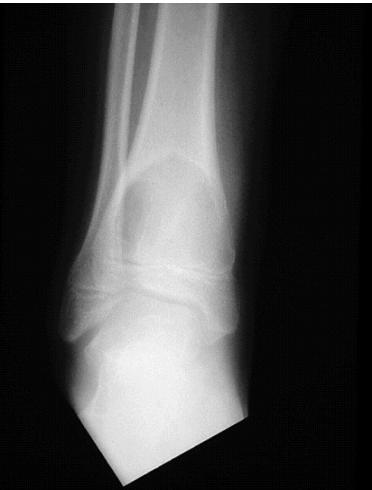

Aneurysmal Bone Cyst

site: Distal tibial

size:  Involving most of distal part

matrix: Cortical expansion, radiolucent matrix, well defined, narrow zone of transition

soft tissue involvement:  no peristeal reaction